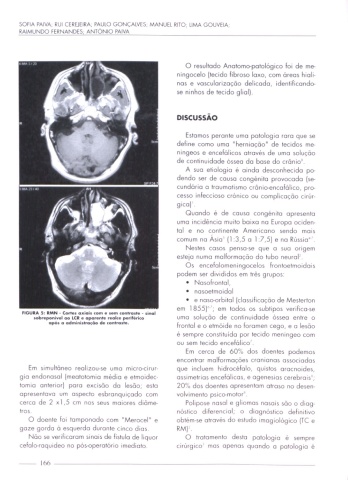

FIGURA 5: RMN - Cones oxiais com o sem <onnus'e - sinal em 1855) em todos os subtipos VCÍIÍICO'SC

sobropomvol oo LCR o apoveme realce porihrico umo soluçao dc contlnmdodc ósseo entre o

apos o odminilnoçõo de contratos.